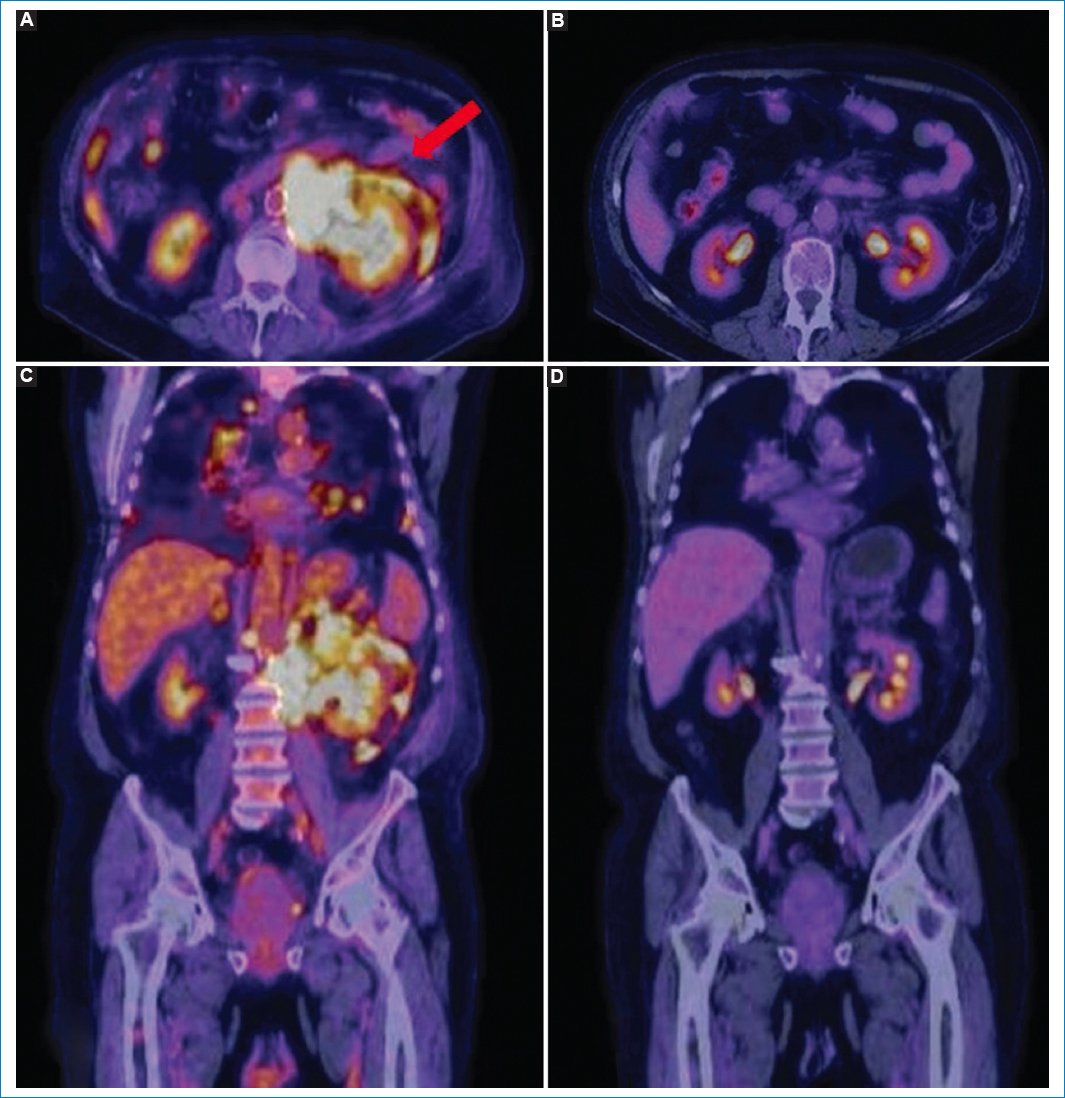

Figura 7. Varón de 65 años con diagnóstico de linfoma difuso de células B grandes y LP. Imágenes de TC (A), fusión PET-TC (B) y MIP (C y D) en las que se puede observar el patrón nodular hipermetabólico del peritoneo (flecha azul) y las adenomegalias en múltiples lugares (flecha roja).

Estos patrones de LP en la PET-TC se acompañan en general de adenomegalias hipermetabólicas múltiples en diferentes sitios, así como de hipermetabolismo esplénico y de la médula ósea, colaborando para el diagnóstico certero y diferencial con las demás afecciones mencionadas (Figs. 12 y 13). Es importante recordar que la avidez de la 18F-FDG varía según el tipo de linfoma involucrado. Así, los linfomas de alta agresividad presentarán mayor metabolismo glucídico que aquellos linfomas indolentes o de bajo grado, variando también su avidez según el grado de respuesta a la quimioterapia instaurada6,19,21 (Fig. 14).